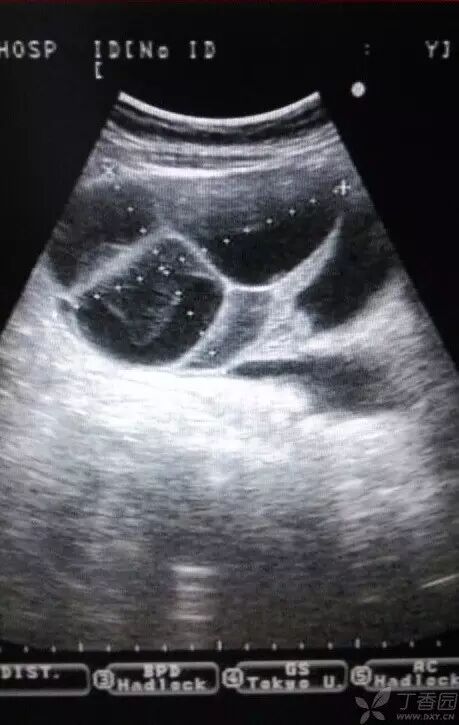

病例2(由丁香园注册用户「荷瓣111」提供):患者女,28岁,结婚5年未孕,应用促排卵药治疗2个月后,自觉腹部膨隆,呼吸困难。

超声所见如下图所示:

图1~3 显示子宫正常,盆腹腔可见两个相依的囊性肿物,其内见多条光带分隔,子宫被压在增大的卵巢下方

图4 显示肝肾区的腹腔积液